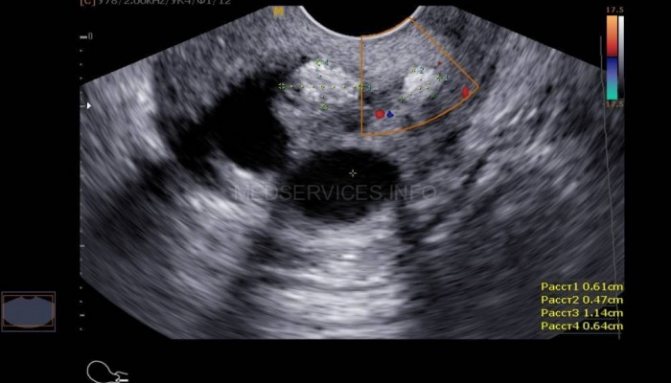

Короткая шейка матки как причина ИЦН (УЗИ)

Патологически короткая шейка матки вызывает опасение и называется в медицине истмико-цервикальной недостаточностью (ИЦН). Ее обычно диагностируют, начиная с 20 недели беременности, при прохождении второго планового УЗИ. До 37 недели орган должен характеризоваться как незрелый. Для этого врачами применяется представленная выше методика. При исследовании на 20–25 неделе беременности врач делает прогноз:

- Если орган имеет длину менее 1 см, роды произойдут на 30–32 неделе.

- Длина 1–1,5 см говорит о появлении ребенка на свет на 33 неделе.

- Если же показатель равен 2 см, предположительно родовая деятельность наступит на 34 неделе.

- Результат измерений в диапазоне 2–2,5 см прогнозирует появление малыша на свет на 36 неделе.